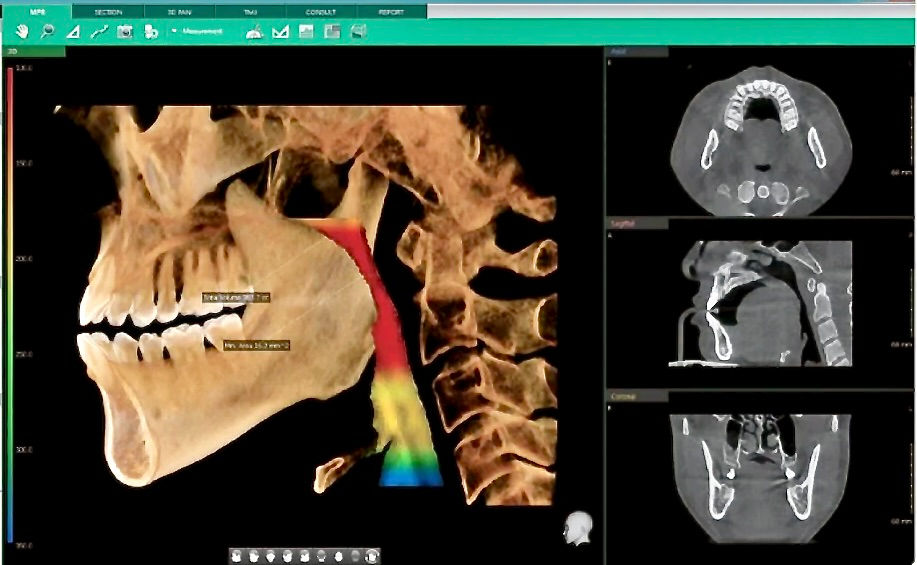

Badania dodatkowe

Zdjęcia cefalometryczne boczne

Badanie przepływu powietrza przez nos

Polisomnografia (badanie snu)

Tomografia komputerowa dróg oddechowych

Zaawansowane metody obrazowania 3D

Cyfrowe planowanie leczenia